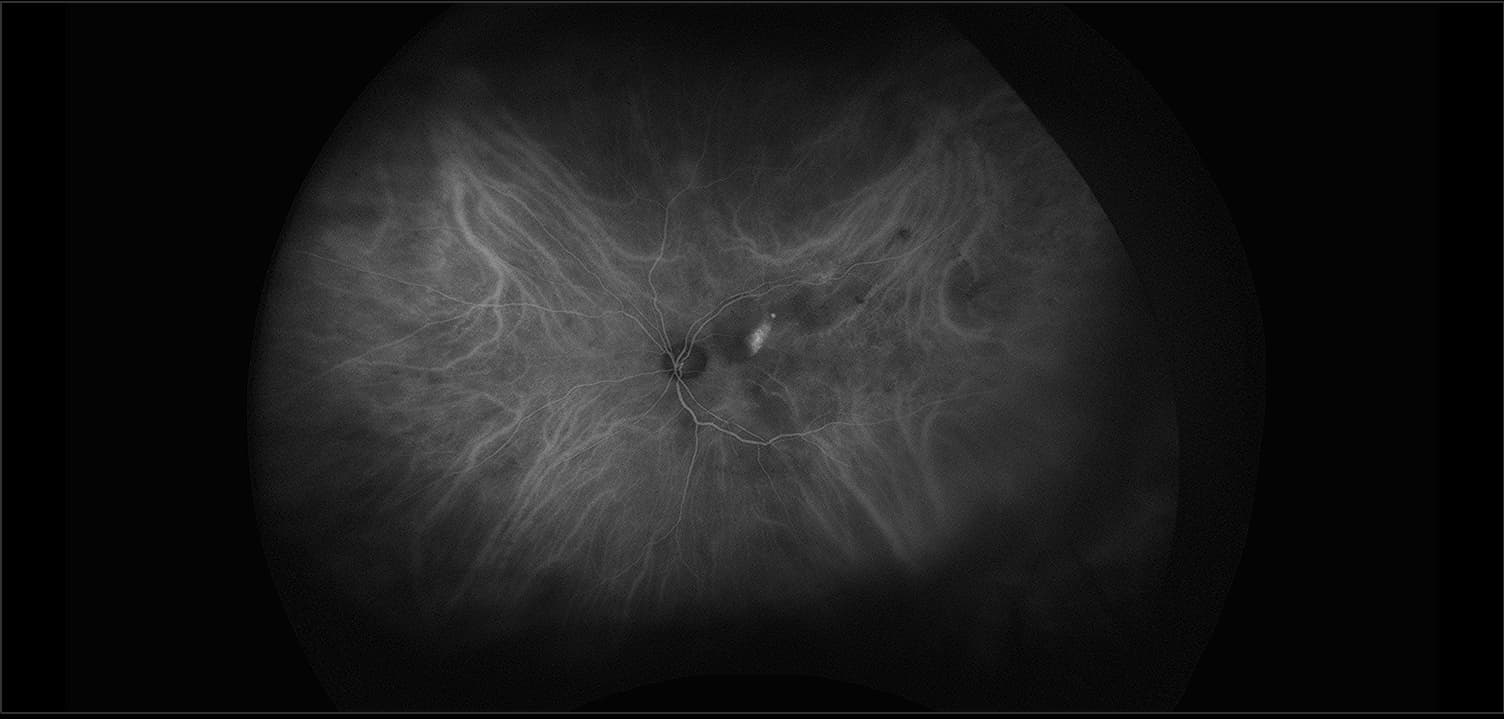

California - Polypoidal Choroidal Vasculopathy, ICG

Polypoidal choroidal vasculopathy (PCV) is a disease of the choroidal vasculature. It is present in both men and woman of many ethnicities, characterized by serosanguineous detachments of the pigmented epithelium and exudative changes that can commonly lead to subretinal fibrosis.